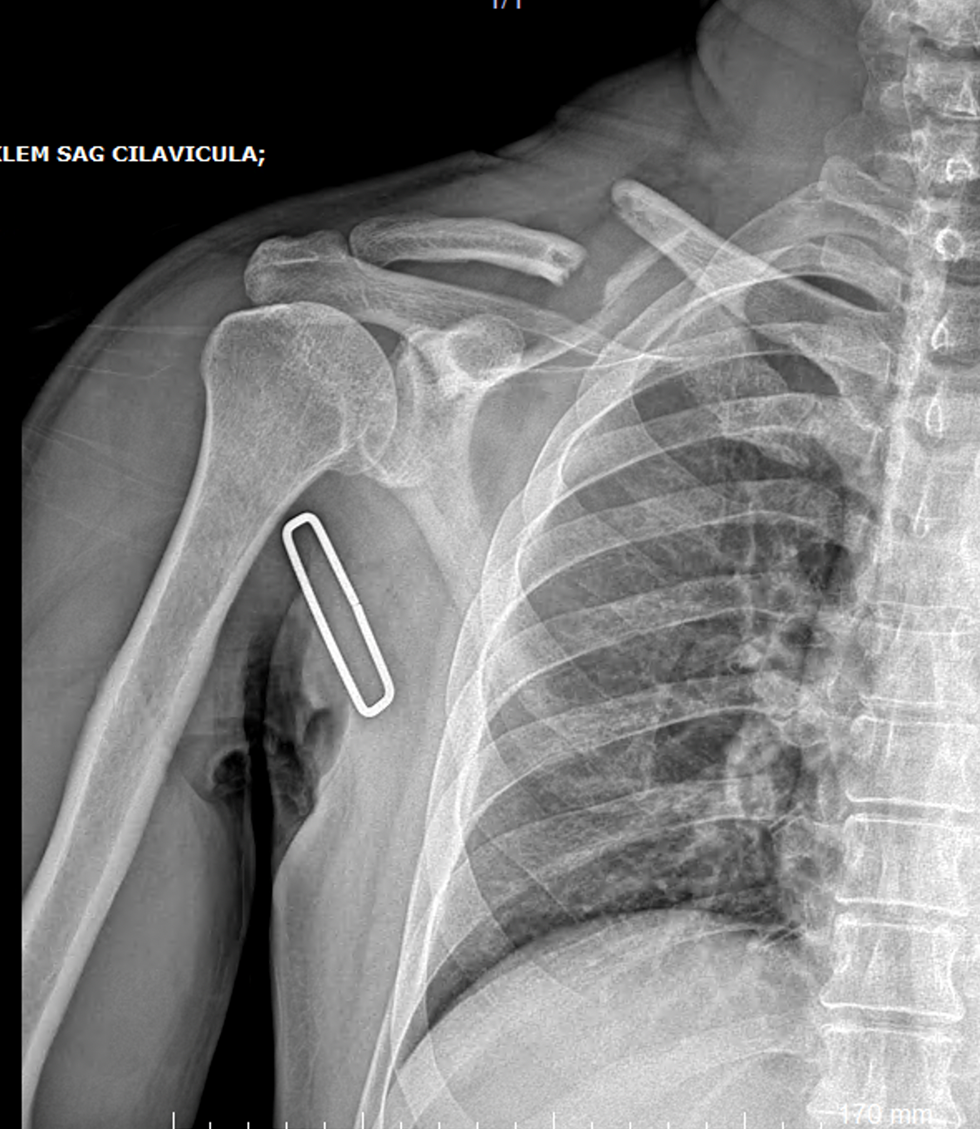

Klavikula kırık ameliyatı

Köprücük kemiği (klavikula) kırık ameliyatı